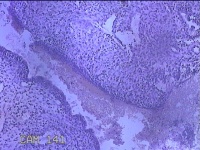

性别

女

年龄

41岁

临床诊断

异常子宫出血;取出子宫内节育器;子宫内膜炎

一般病史

阴道不规则流血2个月。

标本名称

宫腔内容物

大体所见

灰白暗红色不规则碎组织3.5x2.5x0.8cm一堆。